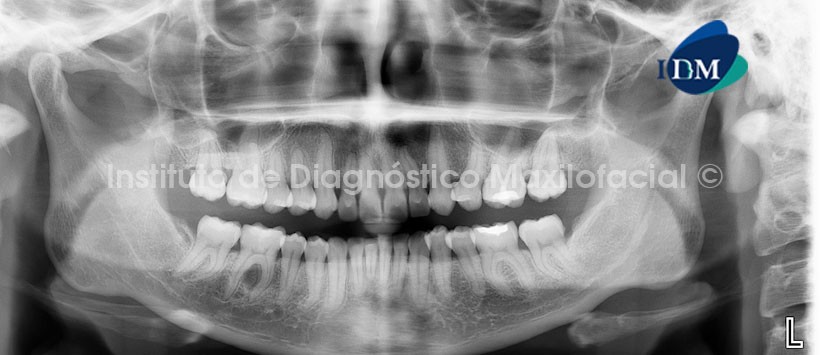

A la evaluación de la radiografía panorámica se aprecia una imagen radiolúcida proyectada a nivel de la furcación de pieza 46 de límites definidos. Aparentemente compromete lámina dura de la zona mencionada. (Figura 1)

A la evaluación de la tomografía volumétrica (CBCT) en cortes axiales (Figura 2), transaxiales (Figura 3) y tangenciales (Figura 4), se evidencia una lesión predominantemente hipodensa con aumento de la densidad en la zona central, de límites definidos, que condiciona adelgazamiento y erosión de la tabla ósea lingual. Así mismo se confirma el compromiso de la lámina dura en la zona de la furcación.

Signos imaginológicos compatibles con lesión fibroósea a descartar Fibroma osificante

Radiográficamente, la imagen frecuentemente observada, aparece como un área radiolúcida, unilocular, bien definida y delimitada por un halo radiopaco (esclerótico); ocasionalmente puede presentarse como una imagen radiopaca. El tratamiento es quirúrgico y consiste en la enucleación total de la lesión.